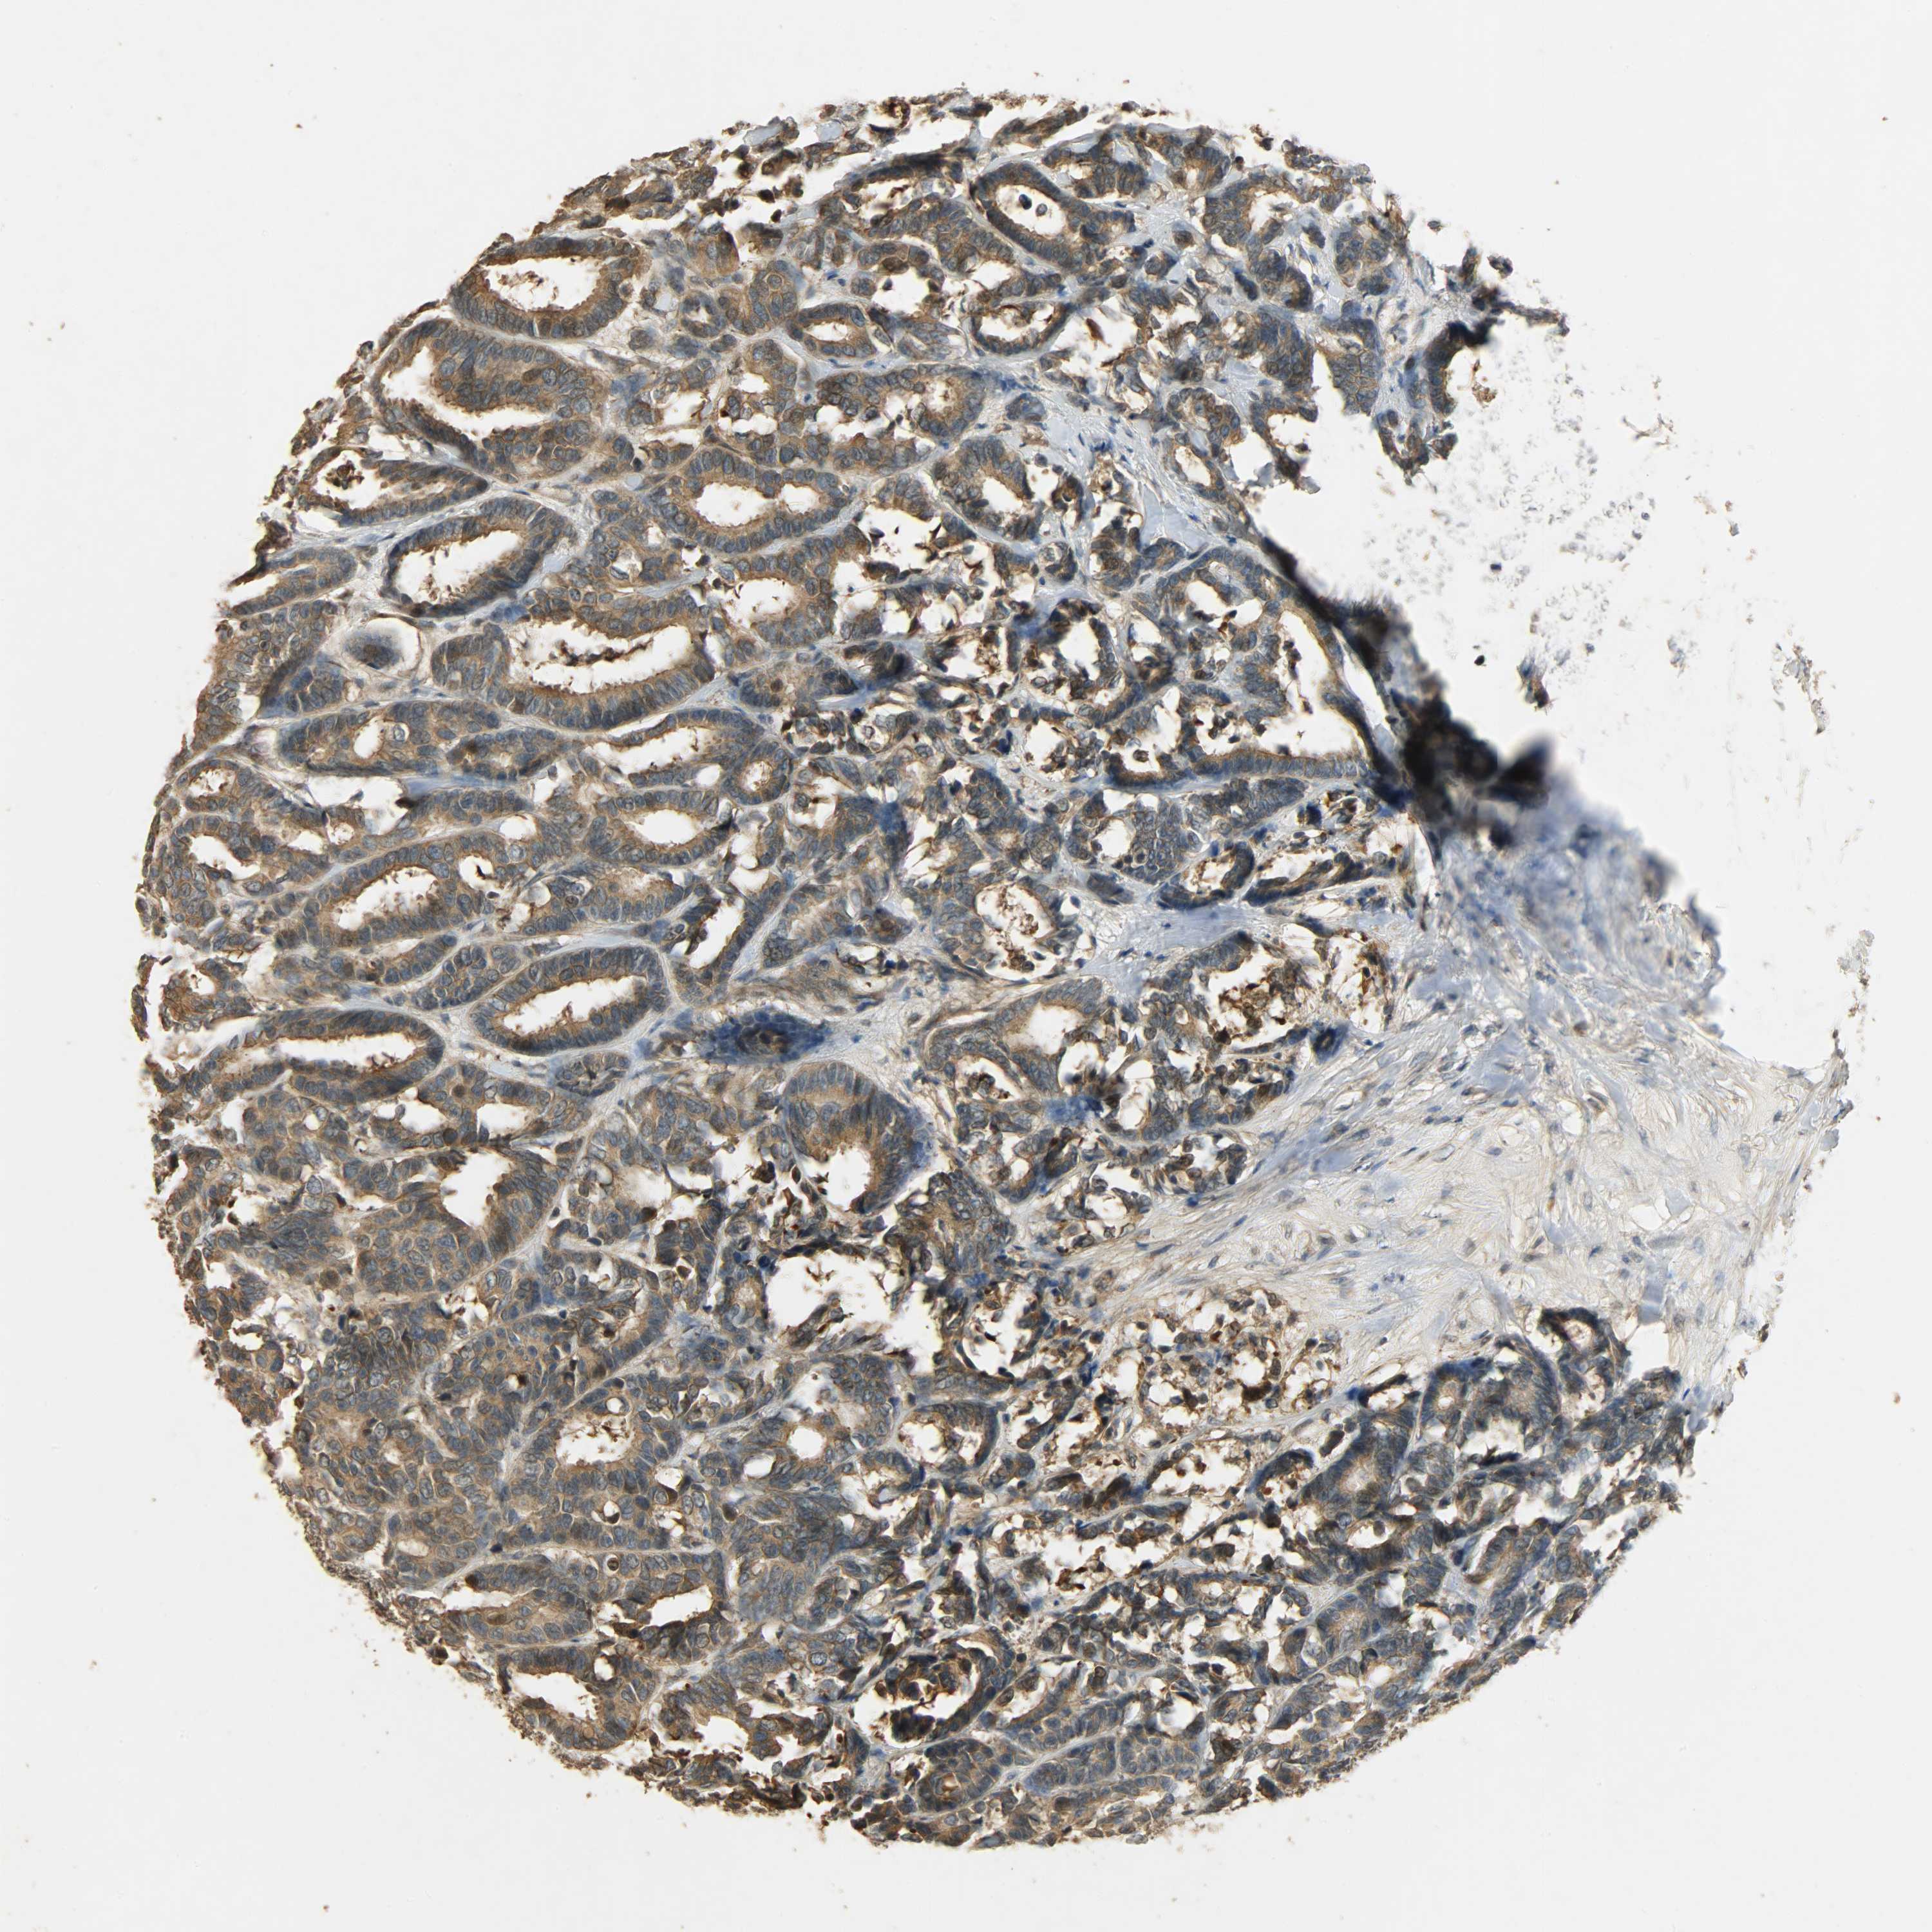

CANCER BREAST CANCER Show tissue menu

BRCA TCGA BRCA VALIDATION PROTEIN EXPRESSION